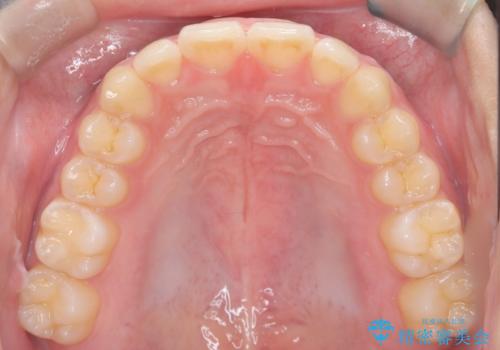

マウスピース矯正で前歯のガタツキを改善! 短期間で治療完了

- 前歯のガタツキが気になるとのことで来院されました。

マウスピース矯正で治療することとしました。

- 1年3ヶ月